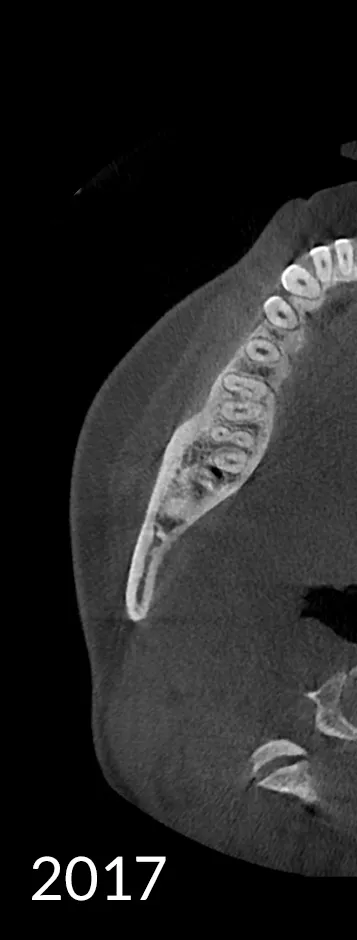

When capturing a CBCT scan, the presence of metal in the oral cavity can introduce artifacts, shadows, and bright streaks that significantly compromise image quality. These distortions may obscure critical anatomical structures, making it more difficult to evaluate bone integrity and surrounding areas—adding complexity to diagnosis and increasing clinical stress.

HDX WILL’s cutting-edge technology now offers a powerful solution through PrecisionMAR™, a metal artifact reduction feature that enhances clarity and ensures more precise imaging—even around metal. This is especially valuable for both dental professionals and ENT specialists focused on comprehensive treatment planning, including airway-focused care.